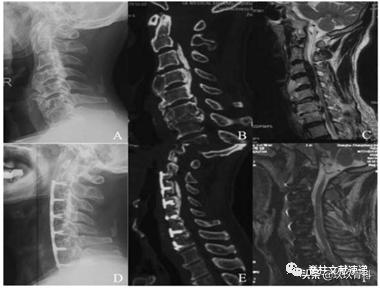

手术操作步骤(下图):A暴露和定位,B椎间盘摘除,C安放椎间融合器并切除椎体前方。D在左侧开槽,并预安装钛板,E在右侧开槽,游离OPLL骨块,F,提拉椎体和骨块。

下面是文中给出的两个病例